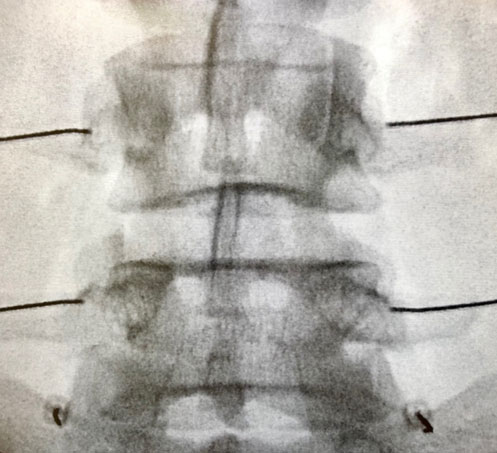

When a person’s facet (zygapophysial) joints are emanating pain, the medial branch nerves will sense this pain signal and transmit it along a pathway to the spinal cord and up to the brain where we interpret and “feel” that painful sensation. As such, medial branch nerve blocks can be used as a diagnostic injection to help determine whether or not the facet joints are the primary source of pain. Using x-ray (fluoroscopic) guidance, needles are safely guided to and placed near the medial branch nerves which are then anesthetized, thus temporarily blocking the pain coming from the facet joints. Patients are then asked to monitor their pain during the time period that the local anesthetic is blocking the facet joint pain. In patients who experience a significant improvement in their pain, it increases the likelihood that the facet joints are the main source of pain and radiofrequency ablation can be performed as a treatment to provide long lasting improvement in the pain. In patients who do not experience much improvement in their pain during the anesthetic phase, it can be determined with much more certainty that the facet joints are not the main source of the pain and the focus can shift to other potential pain generating structures.

After a patient has undergone medial branch nerve blocks to more precisely determine that the facet joints are the primary source of pain, therapeutic procedures may then be considered. These options include radiofrequency ablation of lumbar medial branch nerves (RFA of lumbar MBN), lumbar facet joint injections with corticosteroid (“cortisone”), or lumbar facet joint injections with platelet rich plasma (PRP), all of which are performed using x-ray (fluoroscopic) guidance. With RFA of lumbar MBN, the needle tips are placed in close proximity to the medial branch nerves, the nerves that supply sensation to the painful facet joints). The needle tips are then warmed up to a temperature that causes coagulation or “cauterization” of the medial branch nerves. This disrupts the nerves that sense the pain coming from the facet joints and, consequently, disrupts the pathway for that pain to be sensed and transmitted to the brain. RFA of lumbar MBN can provide long lasting improvement in lumbar facet joint pain, typically 9-18 months at a time, and repeat RFA procedures can be performed time and again to allow for ongoing pain relief for patients. Alternatively, intra-articular lumbar facet joint injections with corticosteroid or PRP can be performed as therapeutic procedures for management of lumbar facet joint pain. Corticosteroid helps to manage pain by decreasing inflammation whereas PRP aids in management of pain by decreasing inflammation and improving signaling of cells that contribute to tissue healing.

As an alternative to PRP injections, lumbar facet joint injections with corticosteroid can be performed to help alleviate low back (lumbar region) pain. Using x-ray (fluoroscopic) guidance, needles are carefully and precisely guided to the painful facet joints. Once the facet joints have been accessed, a steroid solution is instilled through the needle and into the joints. This helps to decrease inflammation and, subsequently, decreases pain and improves function.